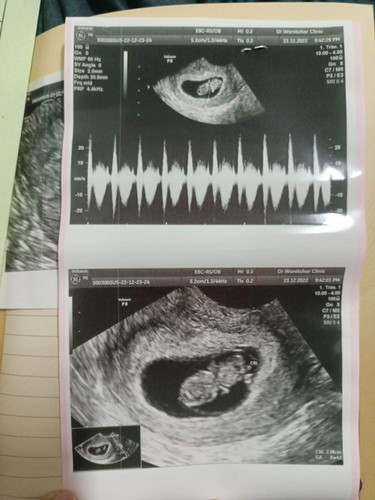

8week2day

ไม่มีจ้า ก่อนเราท้องเรามีพุง3ชั้นเลย ซาวหน้าท้องไม่เห็นอะไรเลย 7วิคเลยได้ซาวด์ผ่านช่องคลอด เห็นตังเล็กตัวน้อยแบบนี้เลยค่ะ เดี๋ยวพอสัก 3เดือนขึ้นไป ก็เห็นแล้วค่ะ ^^

ถ้าหน้าท้องหนาแล้วยังท้องอ่อนๆอยู่ จะซาวด์ผ่านหน้าท้องไม่ค่อยเห็นค่ะ บ้านนี้ตอนฝากท้องได้ 8w ก็อัลตร้าซาวด์ผ่านช่องคลอดค่ะ